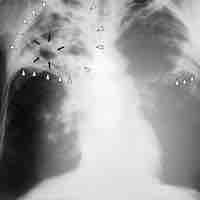

A pathogen or infectious agent is a microorganism such as a virus, bacterium, prion, or fungus that causes disease in its host.

A pathogen's success depends on its ability to evade the host's immune responses.